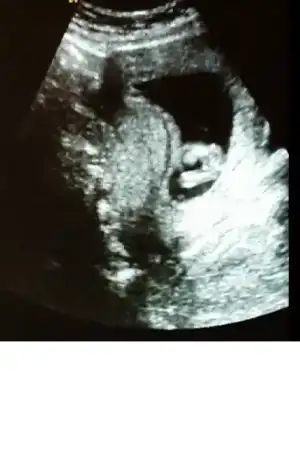

Gijnij merhaba ben seni ve buranin sıkı takipcilerindenim benim de 2 kizim var ALLAH nasip ederse 3 cuye hamileyim 14 haftalik rica etsem resimi eklesem bana yorum edermisin image.webp

ben mesaj atmıştım sana ama sorun oldu gitmedi sanırım. bu fotoda ben nubu çözemedim canım

Sagolasin canim yorumun icin ben 13 haftalikken gittigimde ozeldeki doktor yuzde yetmis erkek demisti 2 li icinde devlete gittim soylemedi ondan merak ettim sordum cnm bu arada senin bana msjin gelmedi gelseydi soylerdim cnm

Bebeğin kız canım hayırlı olsun inşallah

bak buda bacak arası. ama video çekmiştik sanki pipi var gibi geldi bana. acaba kordon mu o? çok kalındı zaten keşke videoyu gönderebilsem sana :).. bu arada yorumun için çok teşekkür ederim canım:KK68:

Canım kızda da erkekte de bu haftalarda çıkıntı oluyor sadece kızın çıkıntılı karşıya bakıyor erkeğin yukarı doğru senin o pipi gibi gösterdiğin karşıya bakıyor kız gibi yani yinede yanılma payı vardır mutlaka